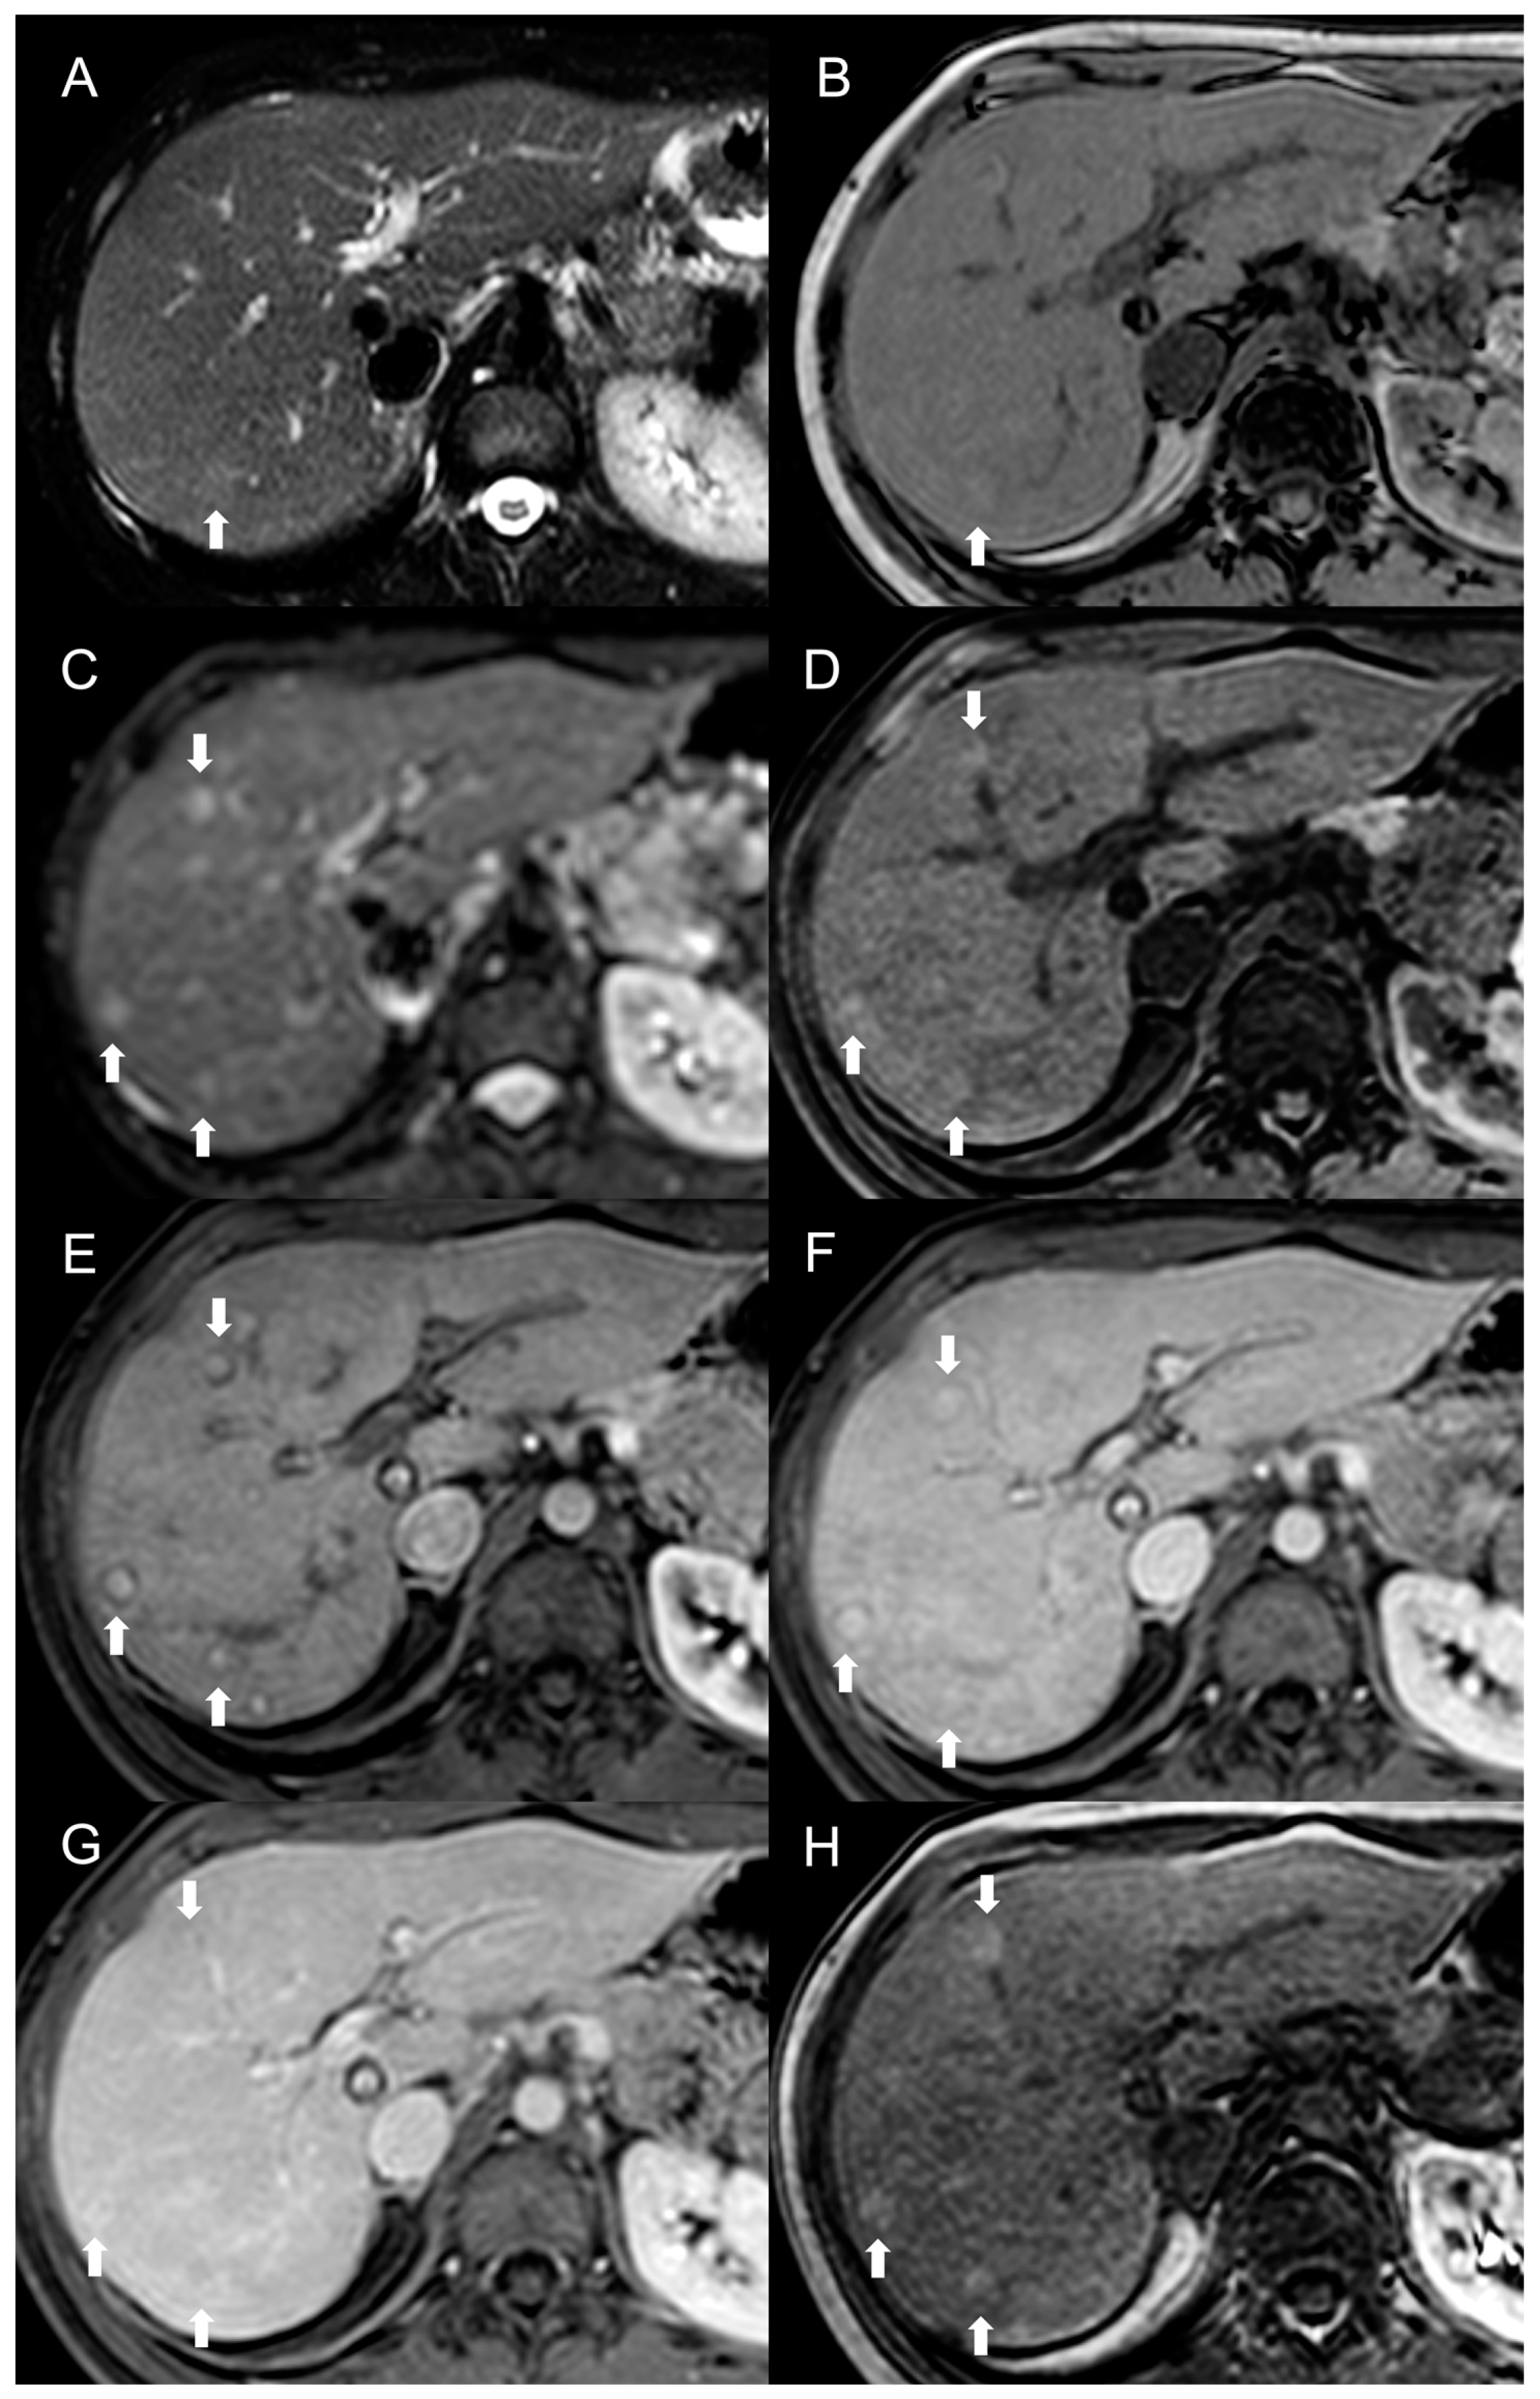

Figure 3.

MRI examination of a 29-year-old female with Budd–Chiari syndrome. On fat-saturated T2-weighted images (A) FNH-like RNs are barely discernable as they appear isointense to the liver parenchyma; occasionally, areas of very slightly hyperintense signal (arrow) can be identified, possibly related to congested nodules or central scar. On out-of-phase T1-weighted images (B) the presence of nodular lesions is more appreciable, as FNH-like RNs (arrow) appear slightly hyperintense compared to the surrounding liver parenchyma. On DWI (b-value = 600) (C), FNH-like RNs may show a slight heterogeneous hyperintensity due to central scar or congestion. On unenhanced gradient-echo T1-weighted images (D), the nodules (arrows) appear hyperintense, while on arterial phase (E) they show vivid enhancement with a peripheral hypointense rim due to hepatic tissue congestion. On portal venous (F) and delayed (G) phases, the nodules become progressively isointense to the liver. On the T1-weighted images (flip angle = 30°) in the hepatobiliary phase (H), FNH-like RNs show hyperintensity compared to the surrounding liver parenchyma.

MRI features of FNH-like RNs are shown in Figure 3.

Besides changes in size, as mentioned above, the MRI features of FNH-like RNs can alter during the follow-up period (Figure 4). For example, the T1 and T2 signal intensity may change, more frequently with a shift from hyperintense to isointense on T1-weighted images and from hypointense to isointense on T2-weighted images. The enhancement pattern may vary as well, with washout acquired in 8% of cases and lost in nearly 20% of cases.

Figure 4.

MRI examinations of a 31-year-old male patient with Budd-Chiari syndrome performed in 2016 (A), 2017 (B), 2018 (C), and 2020 (D). Gradient-echo T1-weighted sequences (flip angle = 30°) acquired in the hepatobiliary phase revealed a 25 mm FNH-like RN (arrows) with central scar and peripheral hyperintensity in 2016 (A). The lesion size grew to 41 mm after 1 year (B) and further to 44 mm after 2 years (C), but it reduced to 35 mm in 2020 (D). Additionally, new FNH-like RNs appeared over time (arrowheads in C,D).